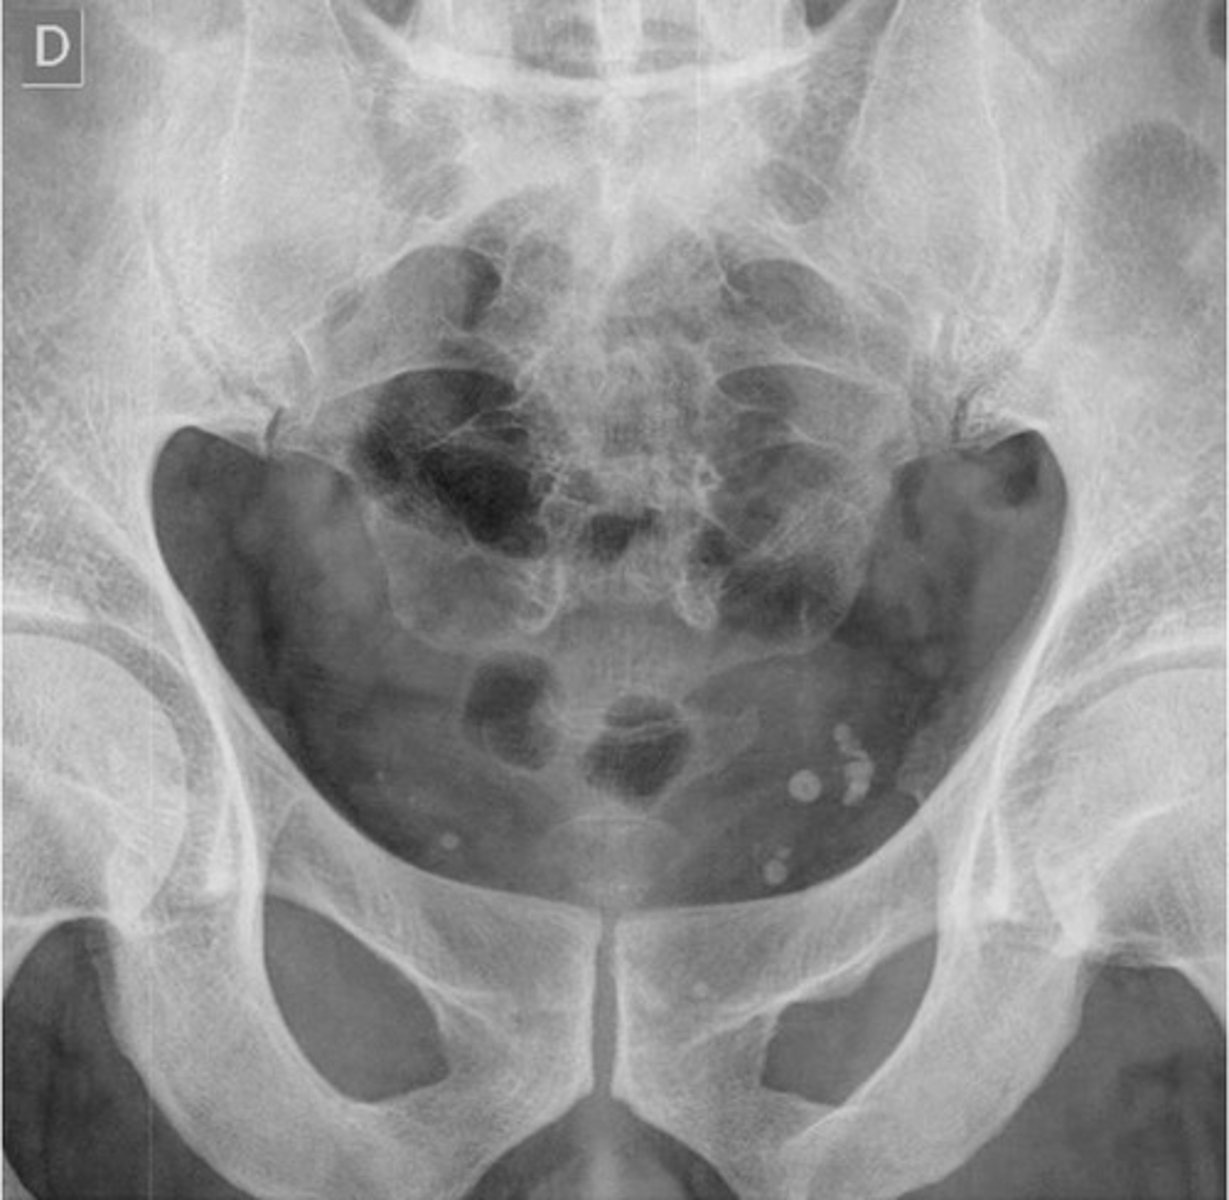

Phleboliths (venous calcifications)